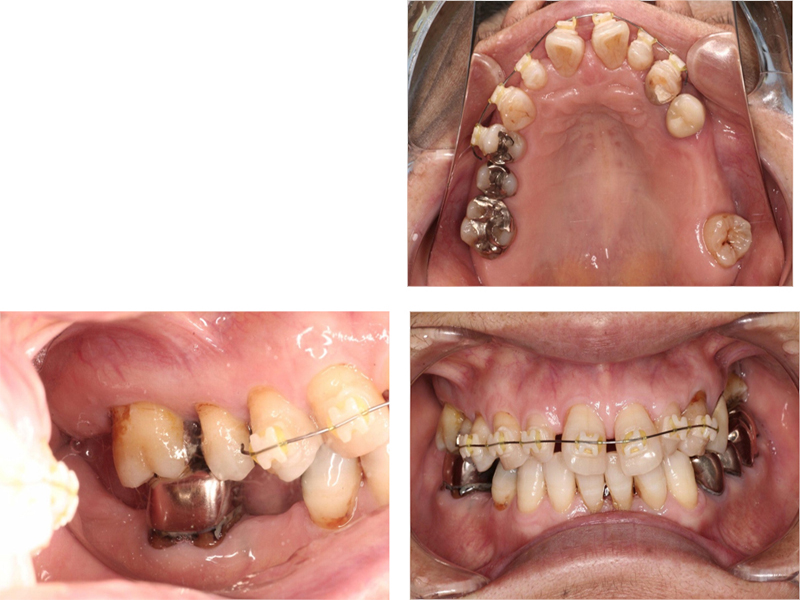

治療中